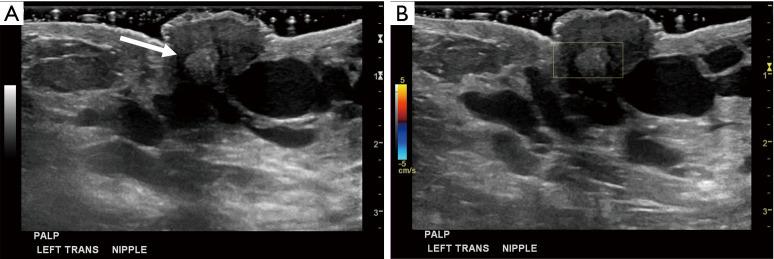

A 34-year-old lactating female presented with a 3-month history of worsening left breast and nipple pain radiating to the left upper outer quadrant, not relieved with conservative therapies. The physical exam revealed a small indentation and a small palpable nodule of the left nipple. There was no associated erythema or redness. Targeted ultrasound and subareolar magnification views revealed findings most consistent with a probably benign inspissated clogged milk duct. Given the patient's history, inability to express milk from the left breast, and plan to lactate for another year, ultrasound-guided aspiration was desired. Post-aspiration images demonstrated complete resolution of the nipple mass. Pathology revealed blood and proteinaceous material, in keeping with the diagnosis of inspissated clogged milk duct. Following the procedure, the patient's symptoms resolved completely.

一名34岁的哺乳期女性,左乳房和乳头疼痛加剧3个月,疼痛放射至左乳房外上象限,保守治疗未能缓解。体格检查发现左乳头有一个小凹陷和一个可触及的小结节。无相关红斑或发红。针对性超声检查和乳晕下放大视图显示的结果最符合可能为良性的浓缩性乳腺管堵塞。鉴于患者的病史、左乳房无法挤出乳汁以及计划再哺乳一年,希望进行超声引导下抽吸。抽吸后的图像显示乳头肿块完全消失。病理检查显示为血液和蛋白质物质,符合浓缩性乳腺管堵塞的诊断。手术后,患者症状完全缓解。